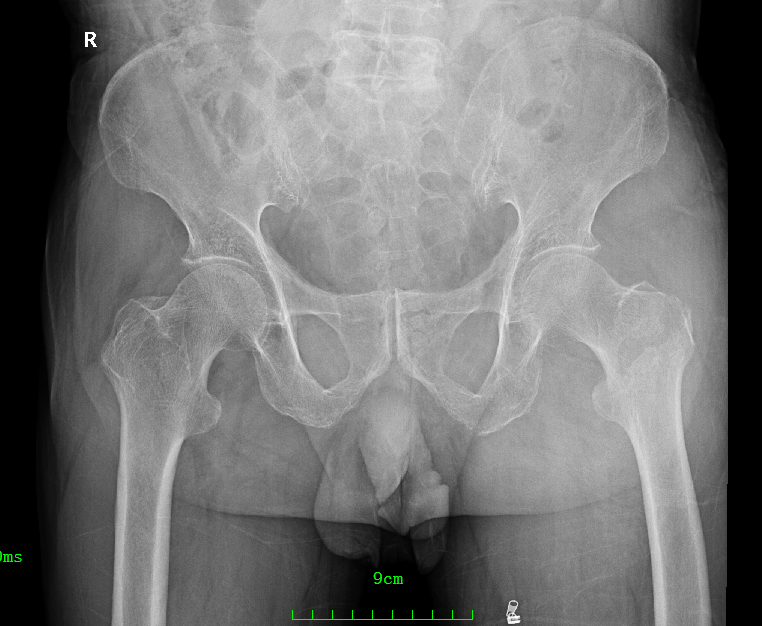

影像资料:

骨盆正位

诊 断:

左股骨粗隆间骨折(Evans Ⅱ);三度房室传导阻滞。